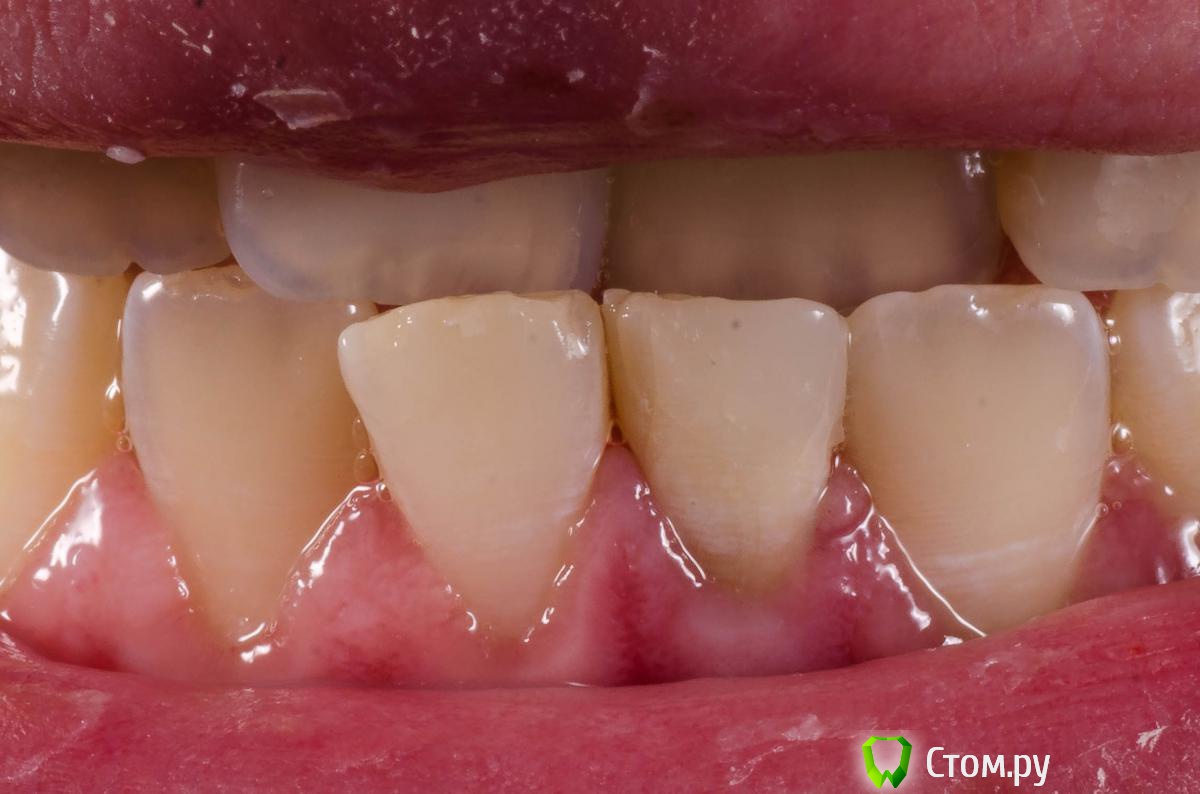

Alexandr Iv Опубликовано 29 июля, 2014 Поделиться Опубликовано 29 июля, 2014 Пациент Н. 14 лет.Диагноз: Хронический гранулирующий периодонтит зуба 3.1Зуб ранее дважды лечен эндодонтически. Корневой канал "обтурирован" проволокой. Был направлен на удаление. Хирург пригласил на консультацию. Решили "спасать". За час под микроскопом извлечена проволока (наверно, это проволока)) ) методом захвата в самодельный цилиндр (из носика для жидкотекучего) и заклиниваем проволоки в цилиндре с помощью 25 к-файла. Обработка и обтурация корневого канала. SoftCore + несколько дополнительных штифтов. Восстановление коронки зуба Filtek Ultimate. Каков на Ваш взгляд прогноз зуба и как Вы видите дальнейшее восстановление коронковой части? Ссылка на комментарий